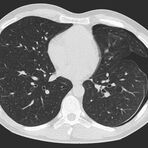

• Entzündungen oder Tumore des Mediastinums und der Lunge

• Lungenembolie- Diagnostik

• hochauflösende Darstellung des Lungenparenchyms zur Abklärung chronischer interstitieller Erkrankungen wie z. B. Fibrosen, Emphysem, Bronchiektasen

Die Zeitspanne für die Untersuchung hängt von der Größe des Untersuchungsbereiches ab. Einzelne Untersuchungen dauern nur wenige Sekunden (die der Lunge z. Bsp. ca. 7 bis 12 Sekunden). Einschließlich Lagerung auf der Untersuchungsliege und der Planung der Untersuchungsbereiche ist eine solche Untersuchung insgesamt meist nach 5 bis 10 Minuten beendet.